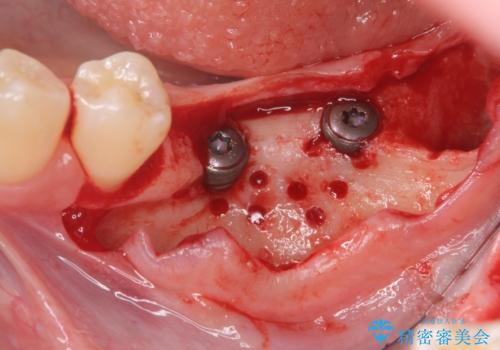

骨造成を行い安定したインプラントの環境を整える治療を計画します。

- 80万円(インプラント×2・骨造成・アバットメント×2)・ジルコニアクラウン×2)費用は治療当時の料金となります

インプラントの長期的な予後を見込むには、インプラント周囲の安定した十分な骨量や清掃性、角化歯肉の存在が重要です。